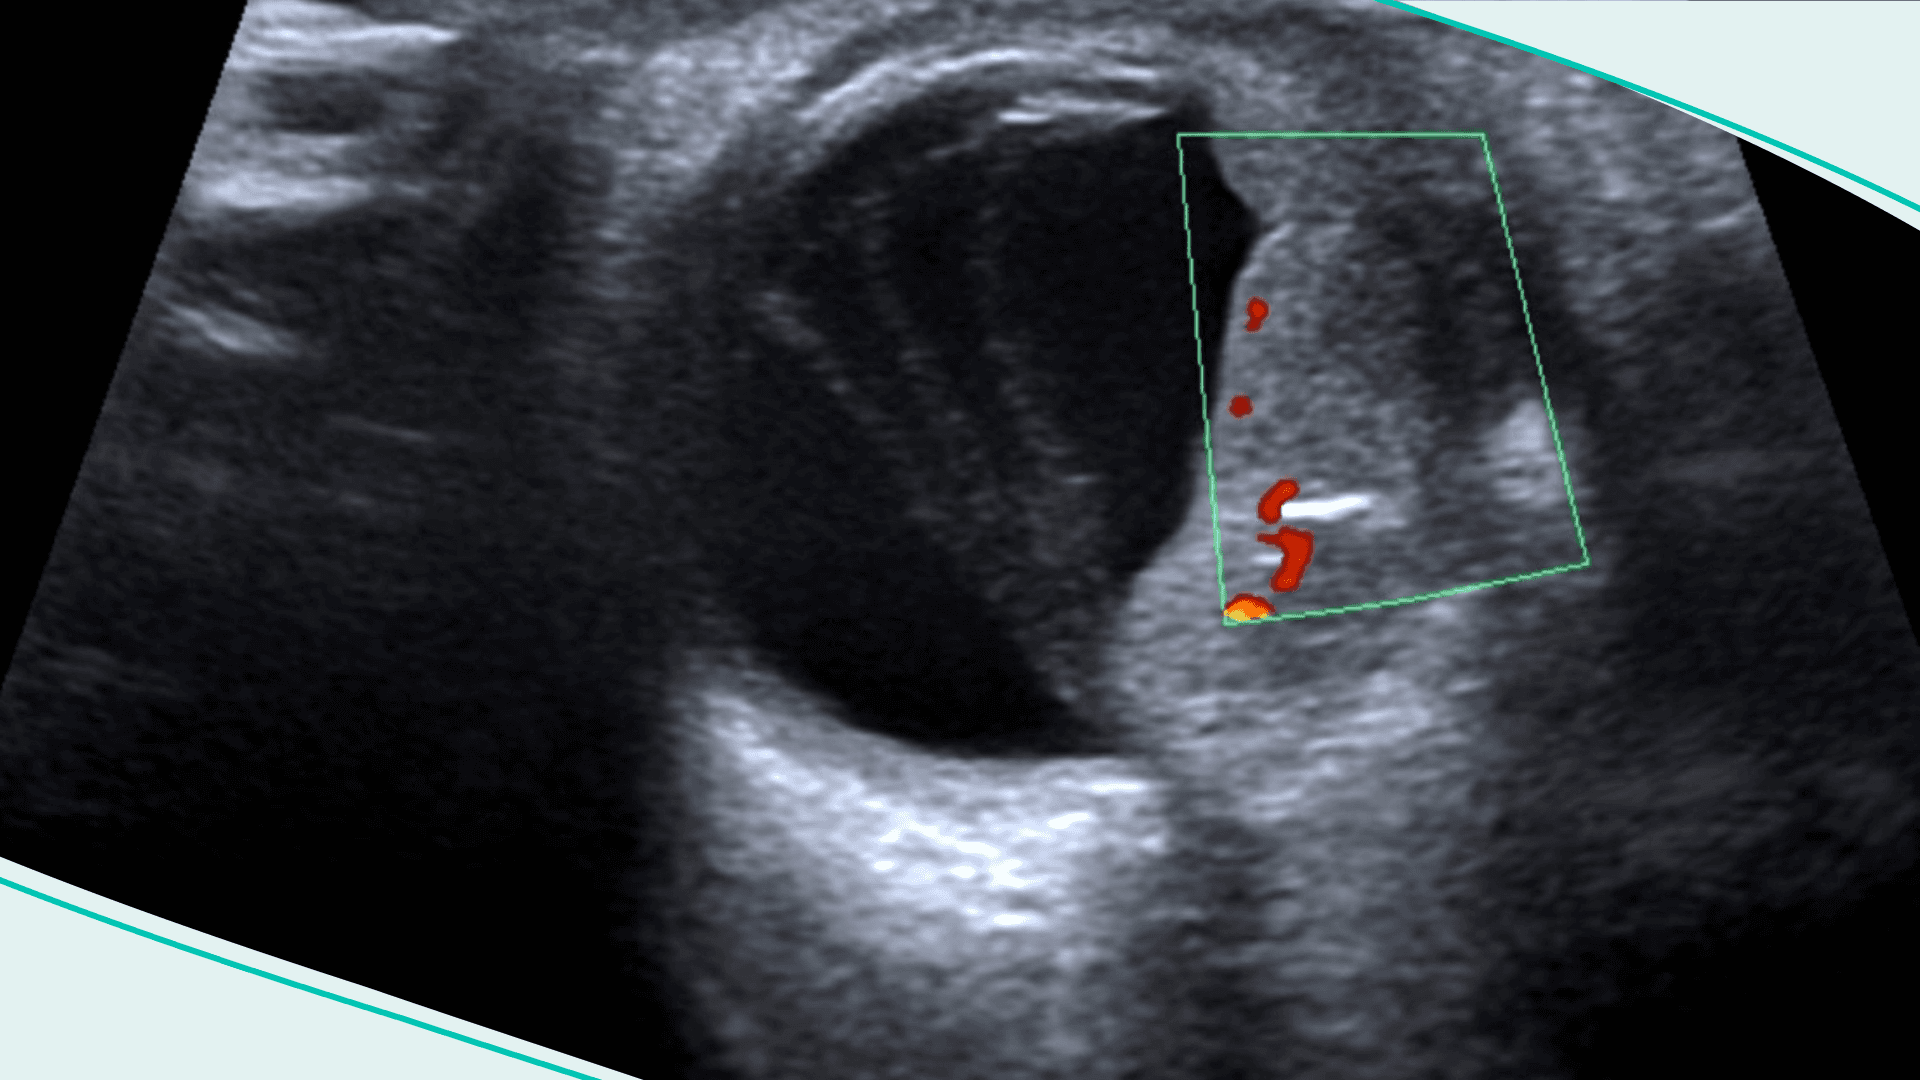

AI can be as good as humans at detecting breast cancer.

This week, a groundbreaking study found that AI was able to detect 20% more cases of breast cancer than humans. It’s not just any study: this was reportedly the first-ever randomized control trial looking into AI and radiology. Over 80,000 women in Sweden were recruited and split into two groups: one whose scans were analyzed by two radiologists, the other by one radiologist and an AI system called Transpara.

Yes. Both groups caught over 200 cases. However, the one with AI caught over 40 cases of breast cancer, without any added false positives. Experts are calling the findings “breathtaking.” The authors are calling for more research. If other studies find similar results, AI could reduce radiologists’ workload by half.

Breast cancer is the most common cancer in the world, with more than 2.3 million women diagnosed annually. AI isn’t replacing doctors anytime soon — but the study raises hopes that it could help catch more cases, earlier.